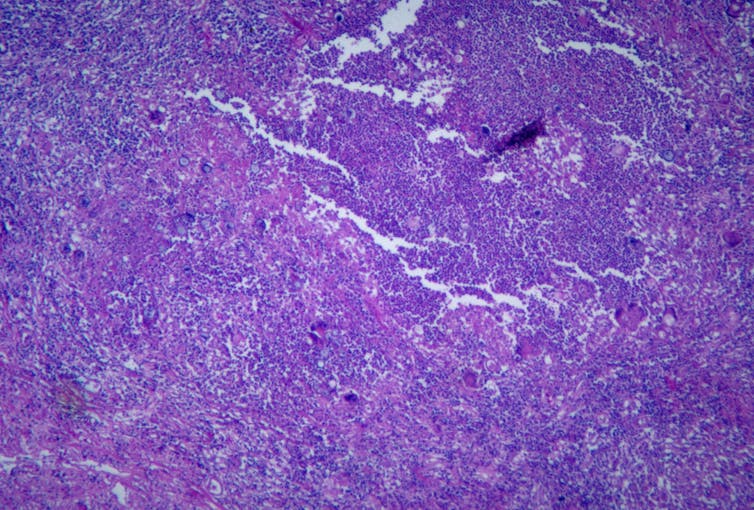

Valley fever is the common name for a disease called coccidioidomycosis, which is an infection caused by pathogenic fungi from the Coccidioides genus. The fungi are primarily found in arid soils of the southwestern United States, as well as parts of Central and South America.

When the fungus has access to moisture and nutrients, it grows long, branching fungal chains throughout the soil. When the soil dries out, these chains fragment to form fungal spores, which can be stirred up into the air when the soil is disturbed, such as by wind or digging. Airborne spores can then be inhaled and cause a respiratory infection.

After inhaling fungal spores from the environment, Coccidioides initially infects the lungs, causing symptoms like mild to severe cough, fever, difficulty breathing, chest pain and tiredness. Valley fever symptoms can resemble other common respiratory infections, so it’s important for people to get checked by a doctor if they’ve experienced prolonged symptoms, particularly if they have been given antibiotics that they are not responding to.

In 5% to 10% of cases, the fungus can spread from the lungs to other parts of the body, such as the central nervous system, liver and bones, causing meningitis or arthritis-like symptoms. These cases can be severe and possibly fatal.